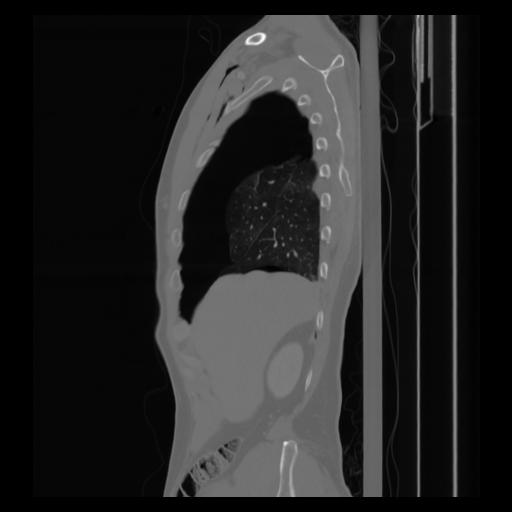

30 CUERPO,CE,Sagittal,3.000,CUERPO,Sagittal,